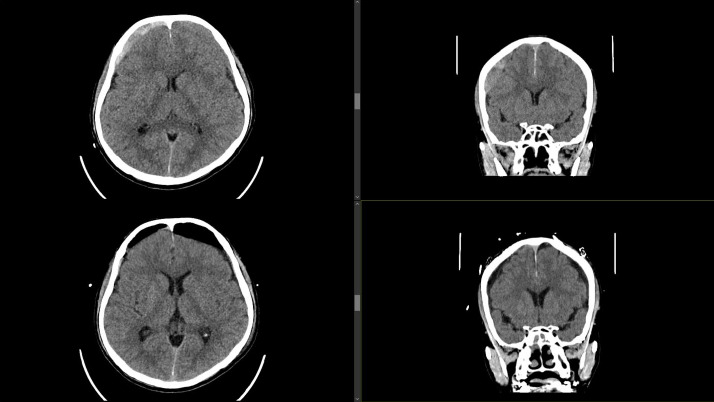

迟发性慢性硬膜下血肿(cSDH)是外伤性脑损伤(TBI)后常见但潜在严重的并发症。轻度脑外伤通常由初级保健提供者(pcp)管理,特别是在像马来西亚这样资源有限的大国家,三级神经外科服务可能会延迟。早期识别危险体征和症状并及时转诊对于防止临床恶化至关重要。我们描述的情况下,66岁的男子谁持续轻度头部损伤后,血管迷走神经性晕厥。他最初的脑部CT显示左侧中央前沟有一个小的外伤性蛛网膜下腔出血,24小时后的间隔扫描解决了这个问题。他没有随访就出院回家了。11周后,他出现双侧下肢无力和步态不稳,这促使他的全科医生紧急转诊。重复CT显示双侧急慢性硬脑膜下血肿,肿块效应需要紧急钻孔引流。患者术后表现良好,第4天出院,后续随访无临床或影像学复发。该病例强调了轻度TBI患者延迟cSDH的风险,即使在那些出院时CT扫描正常的患者中也是如此。pcp在识别高危患者、确保有组织的随访和促进及时的专科转诊方面发挥着关键作用。我们提倡更新马来西亚的头部损伤指南,以国际标准为模型,纳入高危患者的常规随访方案。

Delayed chronic subdural haematoma (cSDH) is a common but potentially serious complication following traumatic brain injury (TBI). Mild TBIs are commonly managed by primary care providers (PCPs), particularly in large, resource-limited settings such as Malaysia, where access to tertiary neurosurgical services may be delayed. Early identification of red-flag signs and symptoms and timely referrals are crucial to prevent clinical deterioration. We describe the case of a 66-year-old man who sustained mild head injury following a vasovagal syncope. His initial brain CT revealed evidence of a small traumatic subarachnoid haemorrhage over the left precentral sulcus, with resolution on an interval scan 24 hours later. He was discharged home without follow-up. Eleven weeks later, he developed bilateral lower-limb weakness and unsteady gait, which prompted an urgent referral by his general practitioner. Repeat CT revealed bilateral acute-on-chronic subdural haematomas, with mass effect requiring emergency burr-hole drainage. The patient showed excellent post-operative improvement and was discharged home on day 4, with no clinical or radiological recurrence on subsequent follow-up. This case highlights the risk of delayed cSDH in patients following mild TBI, even in those discharged with a normal CT scan. PCPs play a pivotal role in recognising high-risk patients, ensuring structured follow-up and facilitating timely specialist referral. We advocate for updating the Malaysian head injury guidelines to incorporate routine follow-up protocols for at-risk patients, modelled after international standards.